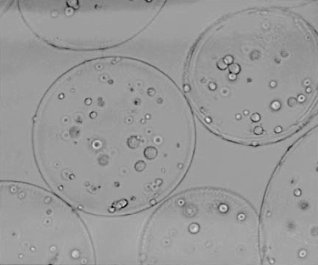

In an article that was published in Endocrinology in 2003, research leader Anthony Atala and first author Marcelle Machluf describe an experiment they did with Leydig cells from rats' testes. Leydig cells produce testosterone. The researchers gently extracted the cells from the tissue, and then attached them to globules of the polymer alginate-poly-L-lysine. The photo below shows the globules under a microscope.